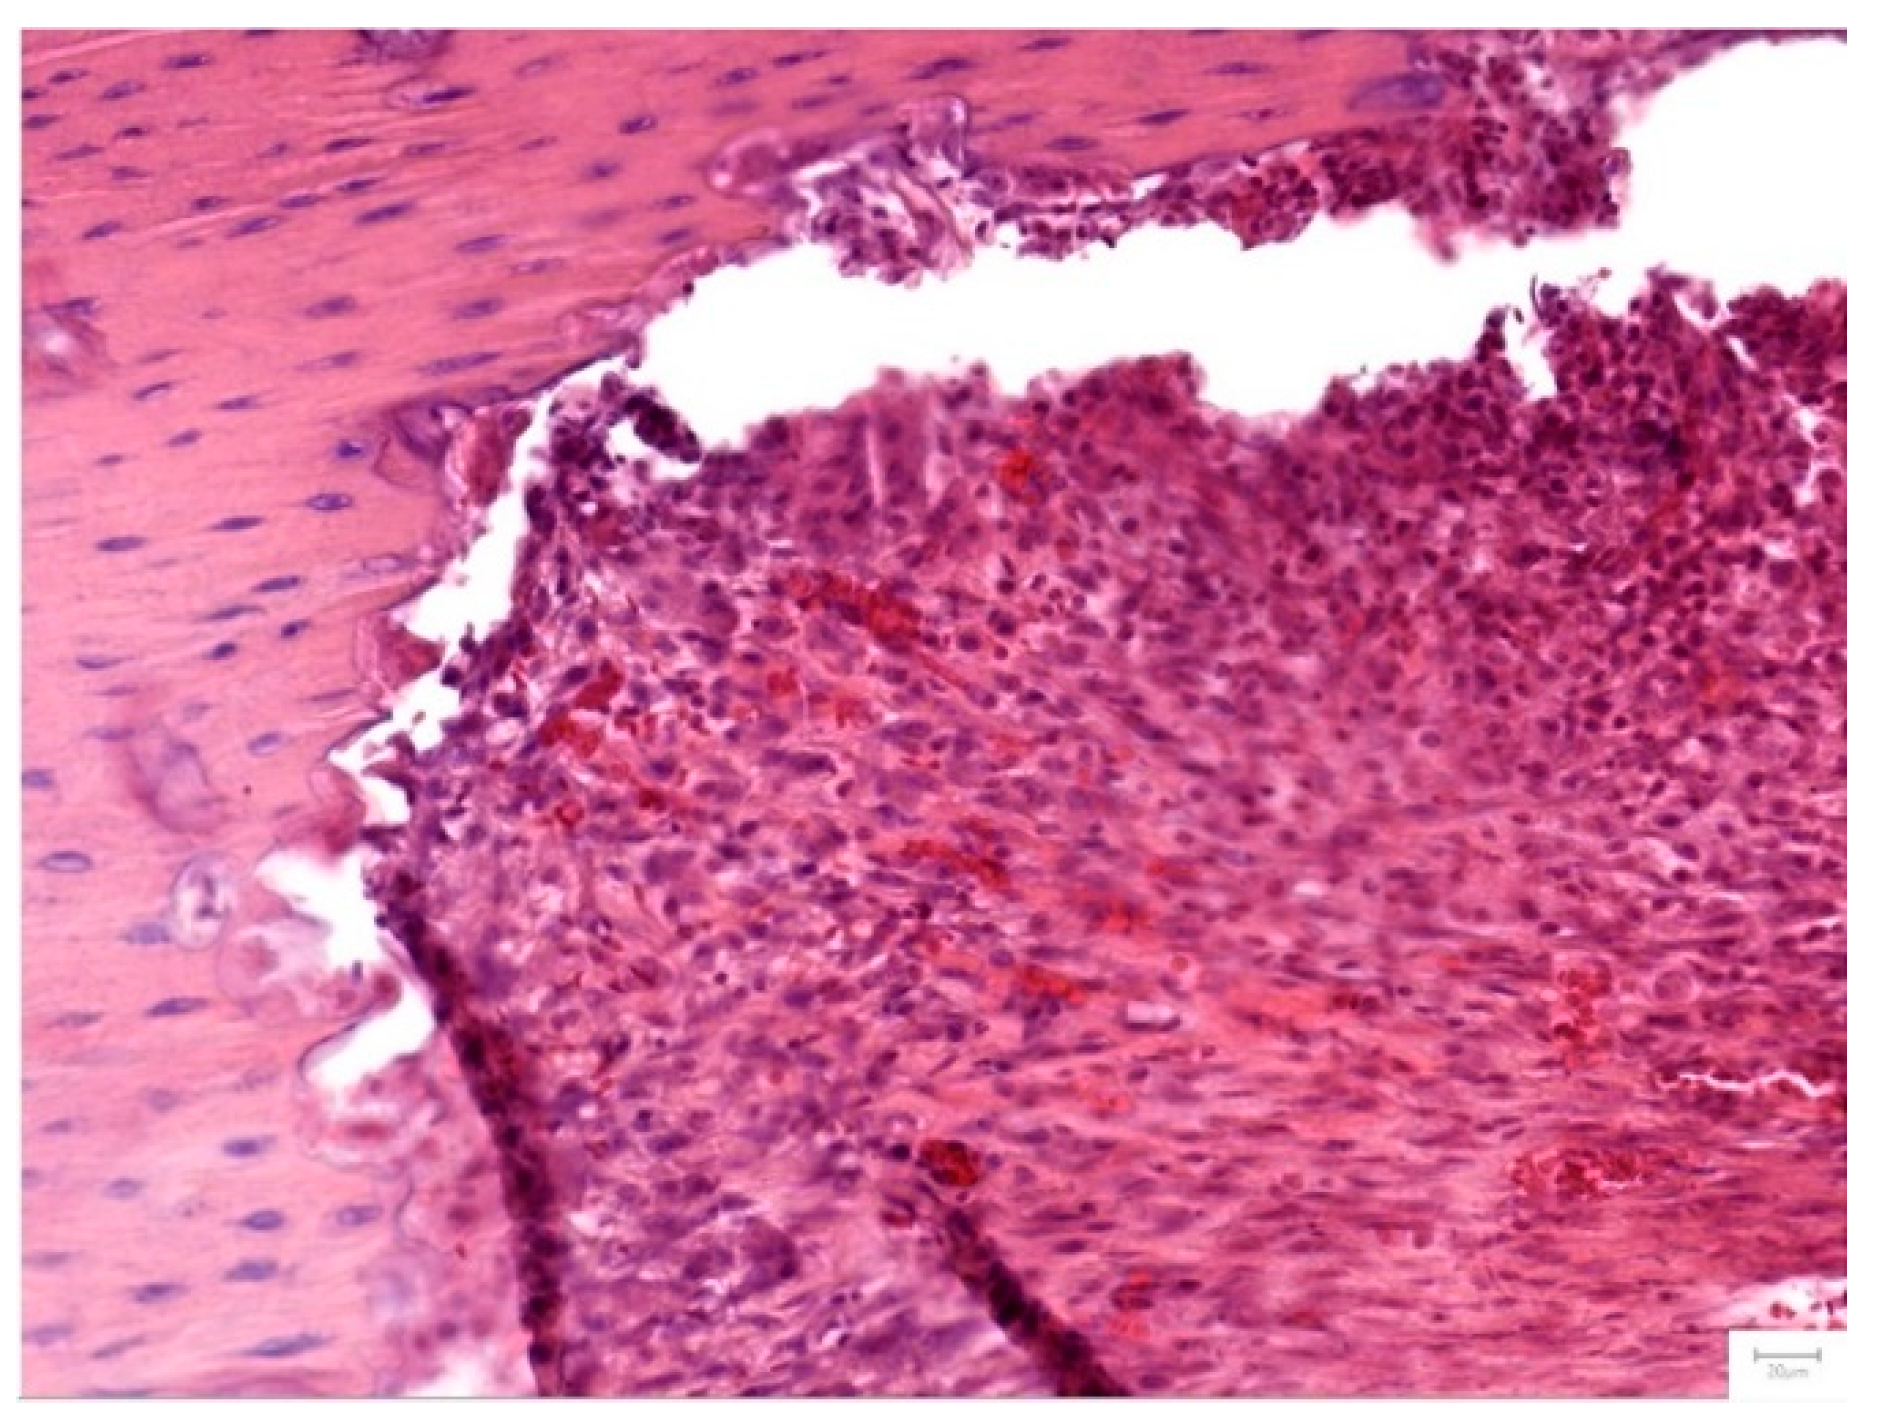

Figure 7. Group I- after 1 month- dense, fibrous irregular connective tissue fills the bone defect area along an abrupt border of the osseous tissue. The dense connective tissue displays a high cellularity, with numerous fibroblasts and a rich, diffuse capillary network, that can be identified throughout the surface of the section, in both the periphery and the central part of the graft area. Low amounts of chronic immune cells and erythrocyte extravasation are also noted (Hematoxylin and Eosine stain, magnification 20 X).